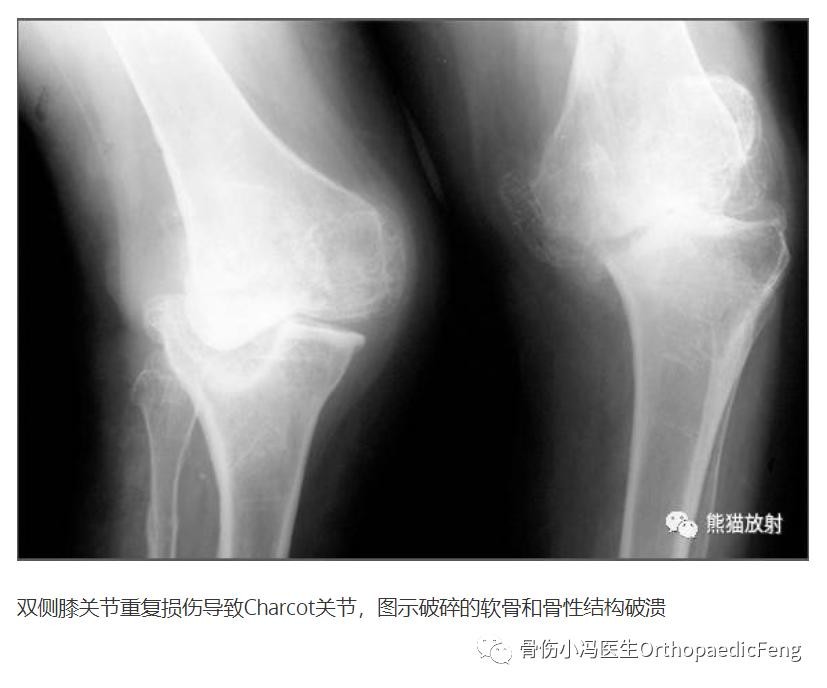

神经性关节病的3大典型X线征象为

1)关节破坏、2)异位新骨形成、3)半脱位

夏科氏关节病X线:分为3型(吸收型、增生型、混合型)

1)早期:积液、软组织肿胀、关节间隙增宽,但关节面无破坏

2)骨融合期:关节腔内游离钙化碎片、软骨下骨密度增高、骨刺形成

3)骨重建期:骨质破坏,关节正常结构紊乱,巨大骨赘,脱落后形成大量的关节内游离体(关节鼠)